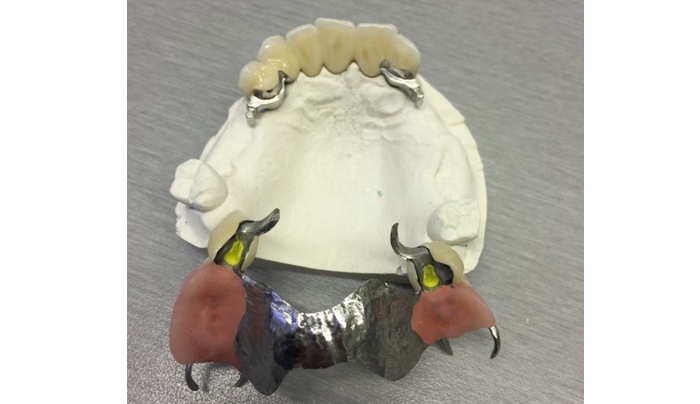

Ukázky naší práce

Kombinovaná práce:

metalokeramický můstek se zásuvnými spoji a částečná náhrada horní s litou patrovou deskou a zásuvnými spoji